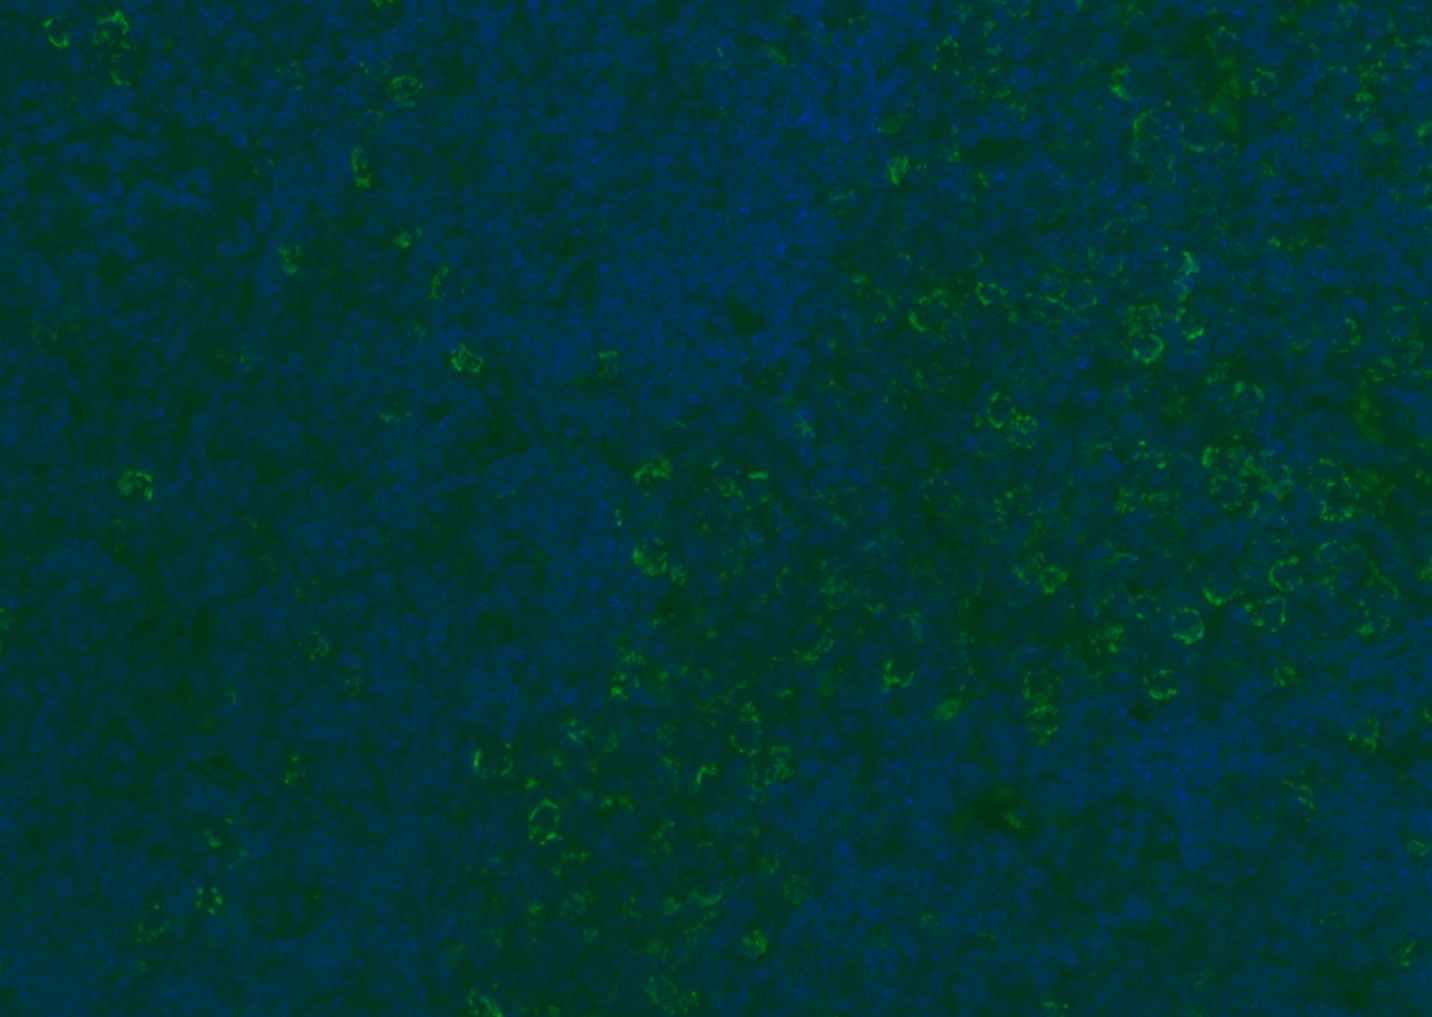

| Verified Activity | 1. Tissue/cell: human lung carcinoma;4% Paraformaldehyde-fixed and paraffin-embedded; Antigen retrieval: citrate buffer (0.01M, pH6.0), Boiling bathing for 15 min; Blocking buffer (normal goat serum) at 37°C for 20 min; Incubation: Anti-CD8 Polyclonal Antibody, Unconjugated (TMAB-00392) 1:200, overnight at 4°C; The secondary antibody was Goat Anti-Rabbit IgG, Cy3 conjugated used at 1:200 dilution for 40 minutes at 37°C. DAPI (5 μg/ml,blue) was used to stain the cell nucleus. 2. Paraformaldehyde-fixed, paraffin embedded (mouse lymphoid); Antigen retrieval by boiling in sodium citrate buffer (pH6.0) for 15 min; Blocking buffer (normal goat serum) at 37°C for 30 min; Antibody incubation with (CD8B) Polyclonal Antibody, Unconjugated (TMAB-00392) at 1:200 overnight at 4°C, followed by a conjugated Goat Anti-Rabbit IgG antibody for 90 minutes, and DAPI for nucleus staining. 3. Paraformaldehyde-fixed, paraffin embedded (rat spleen); Antigen retrieval by boiling in sodium citrate buffer (pH6.0) for 15 min; Blocking buffer (normal goat serum) at 37°C for 30 min; Antibody incubation with (CD8B) Polyclonal Antibody, Unconjugated (TMAB-00392) at 1:200 overnight at 4°C, followed by a conjugated Goat Anti-Rabbit IgG antibody for 90 minutes, and DAPI for nucleus staining. 4. Paraformaldehyde-fixed, paraffin embedded (mouse thymus); Antigen retrieval by boiling in sodium citrate buffer (pH6.0) for 15 min; Blocking buffer (normal goat serum) at 37°C for 30 min; Antibody incubation with (CD8B) Polyclonal Antibody, Unconjugated (TMAB-00392) at 1:200 overnight at 4°C, followed by a conjugated Goat Anti-Rabbit IgG antibody for 90 minutes, and DAPI for nucleus staining. 5. Paraformaldehyde-fixed, paraffin embedded (rat lymphoid); Antigen retrieval by boiling in sodium citrate buffer (pH6.0) for 15 min; Blocking buffer (normal goat serum) at 37°C for 30 min; Antibody incubation with (CD8B) Polyclonal Antibody, Unconjugated (TMAB-00392) at 1:200 overnight at 4°C, followed by a conjugated Goat Anti-Rabbit IgG antibody for 90 minutes, and DAPI for nucleus staining. 6. Paraformaldehyde-fixed, paraffin embedded (rat thymus); Antigen retrieval by boiling in sodium citrate buffer (pH6.0) for 15 min; Blocking buffer (normal goat serum) at 37°C for 30 min; Antibody incubation with (CD8B) Polyclonal Antibody, Unconjugated (TMAB-00392) at 1:200 overnight at 4°C, followed by a conjugated Goat Anti-Rabbit IgG antibody for 90 minutes, and DAPI for nucleus staining. 7. Paraformaldehyde-fixed, paraffin embedded (human tonsil); Antigen retrieval by boiling in sodium citrate buffer (pH6.0) for 15 min; Blocking buffer (normal goat serum) at 37°C for 30 min; Antibody incubation with (CD8B) Polyclonal Antibody, Unconjugated (TMAB-00392) at 1:200 overnight at 4°C, followed by a conjugated Goat Anti-Rabbit IgG antibody for 90 minutes, and DAPI for nucleus staining. 8. Paraformaldehyde-fixed, paraffin embedded (mouse lymphoid); Antigen retrieval by boiling in sodium citrate buffer (pH6.0) for 15 min; Blocking buffer (normal goat serum) at 37°C for 30 min; Antibody incubation with (CD8B) Polyclonal Antibody, Unconjugated (TMAB-00392) at 1:200 overnight at 4°C, followed by a conjugated Goat Anti-Rabbit IgG antibody for 90 minutes, and DAPI for nucleus staining. 9. Paraformaldehyde-fixed, paraffin embedded (rat thymus); Antigen retrieval by boiling in sodium citrate buffer (pH6.0) for 15 min; Blocking buffer (normal goat serum) at 37°C for 30 min; Antibody incubation with (CD8B) Polyclonal Antibody, Unconjugated (TMAB-00392) at 1:200 overnight at 4°C, followed by a conjugated Goat Anti-Rabbit IgG antibody for 90 minutes, and DAPI for nucleus staining. 10. Paraformaldehyde-fixed, paraffin embedded (human tonsil); Antigen retrieval by boiling in sodium citrate buffer (pH6.0) for 15 min; Blocking buffer (normal goat serum) at 37°C for 30 min; Antibody incubation with (CD8B) Polyclonal Antibody, Unconjugated (TMAB-00392) at 1:200 overnight at 4°C, followed by a conjugated Goat Anti-Rabbit IgG antibody for 90 minutes, and DAPI for nucleus staining. 11. Paraformaldehyde-fixed, paraffin embedded (mouse spleen); Antigen retrieval by boiling in sodium citrate buffer (pH6.0) for 15 min; Blocking buffer (normal goat serum) at 37°C for 30 min; Antibody incubation with (CD8B) Polyclonal Antibody, Unconjugated (TMAB-00392) at 1:200 overnight at 4°C, followed by a conjugated Goat Anti-Rabbit IgG antibody for 90 minutes, and DAPI for nucleus staining. 12. Paraformaldehyde-fixed, paraffin embedded (rat lymphoid); Antigen retrieval by boiling in sodium citrate buffer (pH6.0) for 15 min; Blocking buffer (normal goat serum) at 37°C for 30 min; Antibody incubation with (CD8B) Polyclonal Antibody, Unconjugated (TMAB-00392) at 1:200 overnight at 4°C, followed by a conjugated Goat Anti-Rabbit IgG antibody for 90 minutes, and DAPI for nucleus staining. 13. Paraformaldehyde-fixed, paraffin embedded (Rat lymphoid); Antigen retrieval by boiling in sodium citrate buffer (pH6.0) for 15 min; Blocking buffer (normal goat serum) at 37°C for 30 min; Antibody incubation with (CD8B) Polyclonal Antibody, Unconjugated (TMAB-00392) at 1:100 overnight at 4°C, followed by a conjugated Goat Anti-Rabbit IgG antibody for 90 minutes, and DAPI for nucleus staining. 14. Paraformaldehyde-fixed, paraffin embedded (mouse thymus); Antigen retrieval by boiling in sodium citrate buffer (pH6.0) for 15 min; Blocking buffer (normal goat serum) at 37°C for 30 min; Antibody incubation with (CD8B) Polyclonal Antibody, Unconjugated (TMAB-00392) at 1:100 overnight at 4°C, followed by a conjugated Goat Anti-Rabbit IgG antibody for 90 minutes, and DAPI for nucleus staining. 15. Paraformaldehyde-fixed, paraffin embedded (mouse spleen); Antigen retrieval by boiling in sodium citrate buffer (pH6.0) for 15 min; Blocking buffer (normal goat serum) at 37°C for 30 min; Antibody incubation with (CD8B) Polyclonal Antibody, Unconjugated (TMAB-00392) at 1:100 overnight at 4°C, followed by a conjugated Goat Anti-Rabbit IgG antibody for 90 minutes, and DAPI for nucleus staining. 16. Paraformaldehyde-fixed, paraffin embedded (rat spleen); Antigen retrieval by boiling in sodium citrate buffer (pH6.0) for 15 min; Blocking buffer (normal goat serum) at 37°C for 30 min; Antibody incubation with (CD8B) Polyclonal Antibody, Unconjugated (TMAB-00392) at 1:100 overnight at 4°C, followed by a conjugated Goat Anti-Rabbit IgG antibody for 90 minutes, and DAPI for nucleus staining. 17. Paraformaldehyde-fixed, paraffin embedded (rat thymus); Antigen retrieval by boiling in sodium citrate buffer (pH6.0) for 15 min; Blocking buffer (normal goat serum) at 37°C for 30 min; Antibody incubation with (CD8B) Polyclonal Antibody, Unconjugated (TMAB-00392) at 1:100 overnight at 4°C, followed by a conjugated Goat Anti-Rabbit IgG antibody for 90 minutes, and DAPI for nucleus staining. 18. Paraformaldehyde-fixed, paraffin embedded (human tonsil); Antigen retrieval by boiling in sodium citrate buffer (pH6.0) for 15 min; Blocking buffer (normal goat serum) at 37°C for 30 min; Antibody incubation with (CD8B) Polyclonal Antibody, Unconjugated (TMAB-00392) at 1:100 overnight at 4°C, followed by a conjugated Goat Anti-Rabbit IgG antibody for 90 minutes, and DAPI for nucleus staining. 19. Paraformaldehyde-fixed, paraffin embedded (mouse lymphoid); Antigen retrieval by boiling in sodium citrate buffer (pH6.0) for 15 min; Blocking buffer (normal goat serum) at 37°C for 30 min; Antibody incubation with (CD8B) Polyclonal Antibody, Unconjugated (TMAB-00392) at 1:100 overnight at 4°C, followed by a conjugated Goat Anti-Rabbit IgG antibody for 90 minutes, and DAPI for nucleus staining. ![]() ![]() ![]() ![]() ![]() ![]() ![]() ![]() ![]() ![]() ![]() ![]() ![]() ![]() ![]() ![]() ![]() ![]() ![]() |